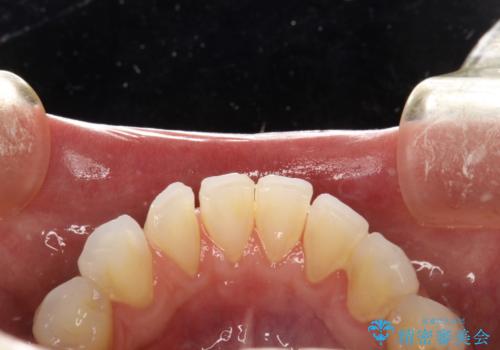

- 痛みや特に気になるところはないが、しっかりとクリーニングしてほしいとのことで来院された患者様です。PMTC 30分コースでのメンテナンスを行いました。

歯を長持ちさせるために、1番の対策が、PMTC を定期的に行うことです。虫歯や歯周病の予防・再発の予防などと、患者様の歯の健康を保つためプロフェッショナルクリーニングを行っています。

痛みや症状が無くても、歯科医院にて専門的なクリーニングを行うことが大切です。